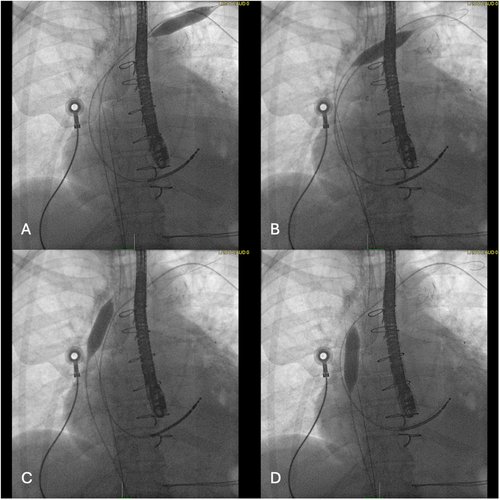

Proud to share the @ClevelandClinic experience on combining Pulsed Field Ablation and Left atrial appendage occlusion that was just published in @hrs_journal. Grateful for the mentorship @omwazni @CleClinicHVTI @Dr_Santangeli @tavrkapadia @CCF_IMCHIEFS #Waeljaber 👇 heartrhythmjournal.com/article/S1547-…